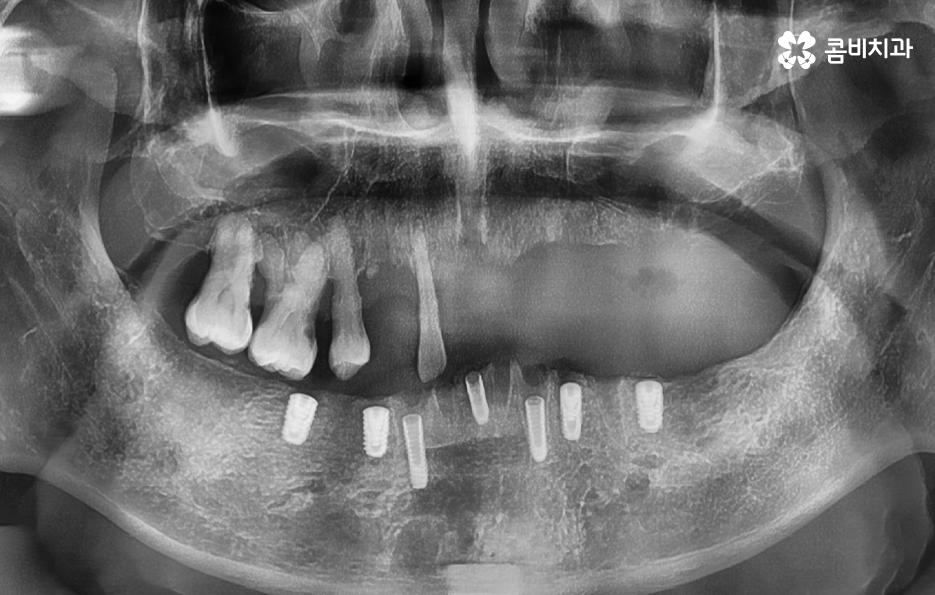

임플란트 브릿지를 활용하여 전체임플란트를 하는 경우 보통 임플란트를 6~8개 정도 식립을 한 후에 임플란트의 머리부분을 연결하여 힘을 분산시키는 방법으로 저작력을 유지시키고 있어요

정리하자면 우선 전체임플란트의 치료 방법은 환자 개개인의 상태를 1:1 맞춤형으로 치료하는 것을 전제로 하되 원칙적으로는 치아를 잃은 만큼 임플란트를 식립하는 것을 권장하고 있어요.

잇몸 상태가 너무 안 좋은 경우에도 치아를 상실한 상태로 그대로 두면 심미적으로나 치아의 기능적으로나 안 좋기 때문에 잇몸 뼈의 상태가 좋은 부분 위주로 골라서 임플란트를 식립하고 브릿지의 형태를 차선책으로 볼 수 있어요